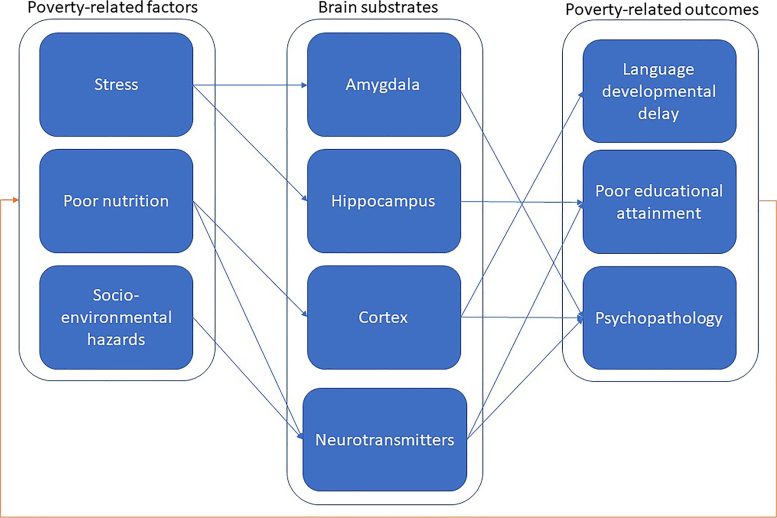

אז איך עוני ו-SES נמוך יכולים לשנות את המוח? הסקירה בוחנת את ההשפעות השליליות של תזונה לקויה, מתח כרוני וסכנות סביבתיות (כגון זיהום ותנאי דיור לא נאותים), אשר נוטים יותר להשפיע על משפחות עם SES נמוך. גורמים אלו עלולים לפגוע בהתפתחות המוחית של ילדים, אשר בתורה יכולה להשפיע על כישורי השפה, הישגיהם הלימודיים והסיכון למחלות פסיכיאטריות.

לדוגמה, משפחות עם SES נמוך נוטות יותר לחוות רמות מתח מוגברות, ואלה יכולים להשפיע על ילדיהן מגיל צעיר. מתח מתמשך יכול להפחית רמות של נוירוגנזה – צמיחה של נוירונים חדשים – בהיפוקמפוס, מה שעלול לפגוע ביכולות הלמידה ולהשפיע לרעה על הישגים לימודיים והזדמנויות קריירה בשלב מאוחר יותר בחיים.

מסגרת של גורמים הקשורים לעוני והשלכות עתידיות, כגון עיכוב בהתפתחות השפה, הישגים לימודיים לקויים וחריגות עצביות. קרדיט: Eid Abo Hamza et al./De Gruyter

המסגרת המאוחדת שהציעו החוקרים עוזרת גם להסביר את העוני הדורי, שעלול להשאיר את ילדי משפחות SES ללא יכולת להימלט ממצבם כשהם גדלים ויהפכו להורים בעצמם. מעגל הקסמים הזה יכול להיות קשה לשבור.

הסקירה הגיעה בזמן, ככל שהאי-שוויון בחברה מתרחב. זיהוי מנגנונים ספציפיים מאחורי עוני דורי יכול לעזור לחוקרים ולקובעי מדיניות לפתח התערבויות מוקדמות חדשות. המסגרת החדשה לוקחת בחשבון את האופי הרב-גורמי של עוני דורי, ועשויה לסלול את הדרך להתערבויות חברתיות הוליסטיות ומתוחכמות יותר שמכירים במורכבות זו.